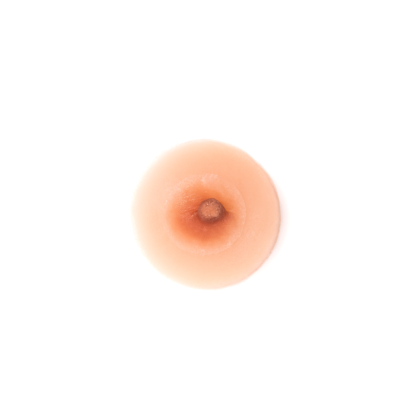

Nuestras prótesis de silicona paramédica de areola y pezón son el accesorio perfecto para quienes buscan una solución estética y reconfortante. Fabricadas en silicona de grado médico, estas prótesis son suaves al tacto, ligeras y diseñadas para imitar la apariencia natural. Son ideales para mujeres que han pasado por mastectomías, cirugías o simplemente desean un mayor realce. Con un diseño ergonómico, se ajustan cómodamente a la piel, brindando seguridad y confianza en cada uso. Disponibles en varios tonos para adaptarse a diferentes tonos de piel, estas prótesis son la opción perfecta para recuperar la feminidad y sentirse bien en cualquier situación.

| Cantidad | SINGLE, DOUBLE |